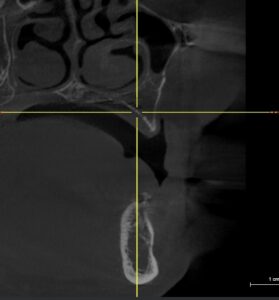

파노라마 엑스레이에서 보면 뼈가 충분해 보여서 쉽게 치료가 될 것으로 생각했지만 CT를 확인한 바 골의 폭경이 아주 좁아서 임플란트 식립에 어려움이 예상되었습니다.

CT로 보면 골질이 안좋고 골폭이 좁아

그런데 CT상으로 관찰한 바로 뼈가 있기는 한데 굉장히 무른 상태이고, 폭이 매우 좁아져 있었습니다. 치아를 뽑고 틀니를 오래 사용하신 분들 중 이렇게 뼈가 많이 약해져 있는 경우가 많습니다.